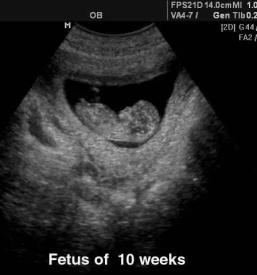

V naši ambulanti se vedno trudimo imeti čimbolj strokoven pristop. To lahko dosežemo le z nenehnim izobraževanjem in spremljanjem razvoja medicinskih postopkov doma ter v tujini. Tako smo se med drugim specializirali za različne preglede, kot je nuhalna svetlina Ptuj.